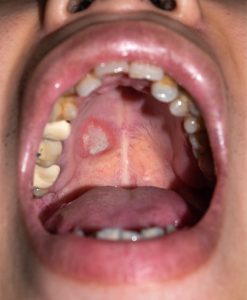

Persistent Mouth Sores: Ulcers or sores that don’t heal within two weeks, especially those that bleed easily or are painless, may indicate cancerous or precancerous conditions requiring immediate evaluation.- Red or White Patches: Unusual colored patches in the mouth, known as leukoplakia (white) or erythroplakia (red), can be early signs of cancer development, particularly on the tongue, floor of the mouth, or inner cheeks.